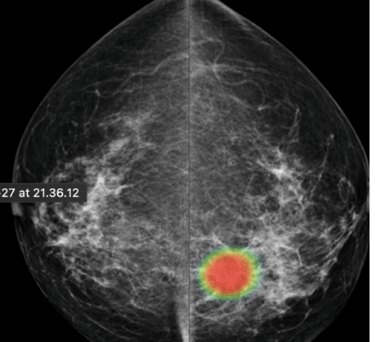

DAM - Breast Solution

To help radiologists improve the predictive accuracy of screening mammography, we present a deep learning method that can detect breast cancer on screening mammograms using a "end-to-end" training technique that efficiently leverages training datasets with either full clinical annotation or merely the cancer status (label) of the entire image. Our training data include biopsy confirmed types of benign or malignant tumors.

Breast cancer detection

Tumor type classification

Breast cancer metastases localization